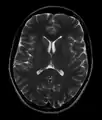

- T1-weighted (T1W) images: Cerebrospinal fluid is dark. T1-weighted images are useful for visualizing normal anatomy.

Brain regions on T1 MRI